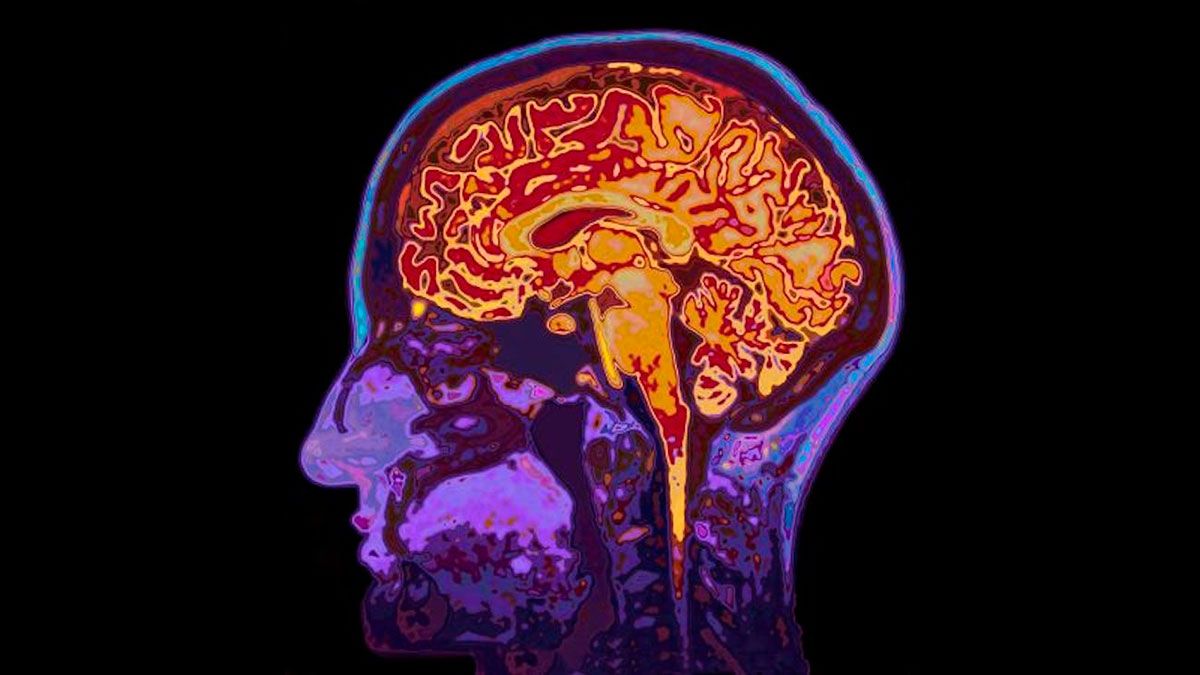

Según se supo, Willis sufre de afasia, un trastorno adquirido del lenguaje que afecta la habilidad de una persona para comprender y/o producir el lenguaje, sin afectar la inteligencia. Afecta la estructura del lenguaje, y la mayoría de las personas afásicas experimentan, además, dificultad para leer y escribir.

Entre las causas de la afasia, la más común es el ACV: cerca del 25-40% de los sobrevivientes de ACV tienen afasia. También puede aparecer como resultado de una injuria cerebral por un traumatismo craneoenceflálico o un tumor cerebral, entre otras.